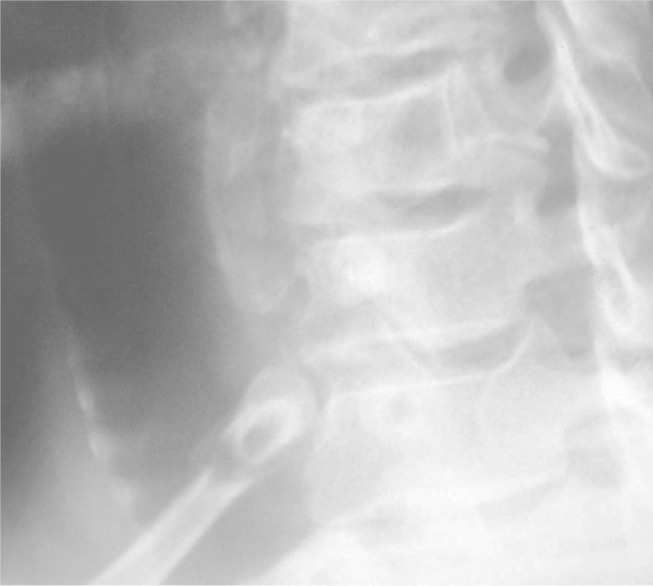

Forty-eight hours after the accident, he complained about pain in the right scapular region, which led him to undergo radiological investigation of the chest and neck, which showed bilateral fracturing of the first rib. The radiological evaluation consisted of anteroposterior (AP) and lateral radiographs of the chest, and AP and right and left lateral and anterior oblique radiographs of the cervical column. The fractures were seen on the AP radiographs (Figure 1) and shown best on the oblique projections of the neck (Figure 2). On the left side, avulsion of the transverse apophysis was associated with the fracturing of the first rib (Figures 3 and 4). Both the fractures were on the posterior part of the rib body.

Figure 2.

Radiograph of the neck in left anterior oblique projection, showing the fracture of the right first rib